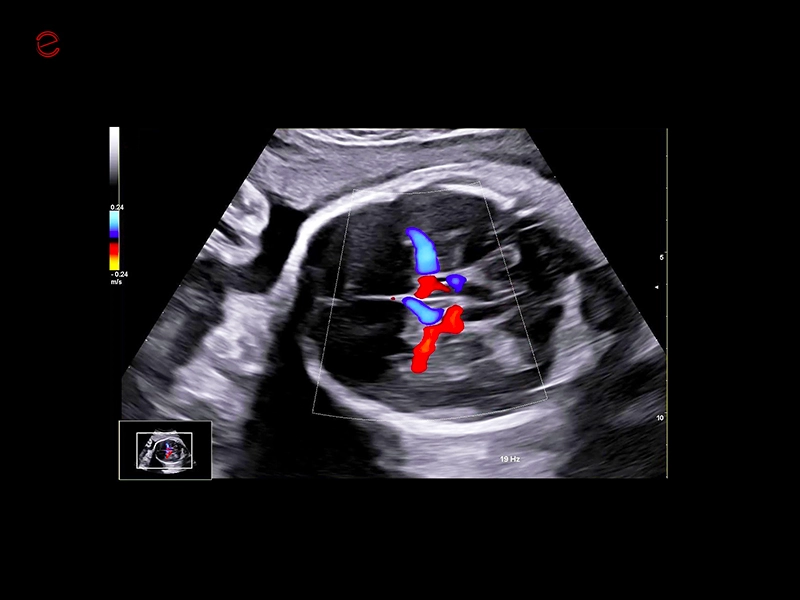

The MyLab™C30 compact ultrasound machine is specifically designed to meet the demands of everyday clinical practice for fast ultrasound access, versatility of use, and space constraints. All this has been achieved without compromising image quality and ultrasound performance. By sharing advanced imaging technologies and transducers with our high-end systems, the MyLab™C30 delivers high quality images and clinical information in a truly compact ultrasound device.

Elevated performance for enhanced diagnostic insights

Featuring the ClearWave Architecture, which combines Esaote’s advanced XBeamforming and XSmart Postprocessing technologies, the MyLab™C30 incorporates state-of-the-art imaging technologies to set a new standard for image quality, giving professionals diagnostic confidence wherever they need it. Maximize the performance of the MyLab™C30 with its wide range of probes for all clinical needs, from daily routine to the most advanced expectations. Equipped with a wide range of advanced features and an accelerated workflow powered by Artificial Intelligence, the MyLab™C30 is your portable ultrasound device that knows no boundaries.

Rely on experience: CAmed Medical Systems is your strong partner in medical technology